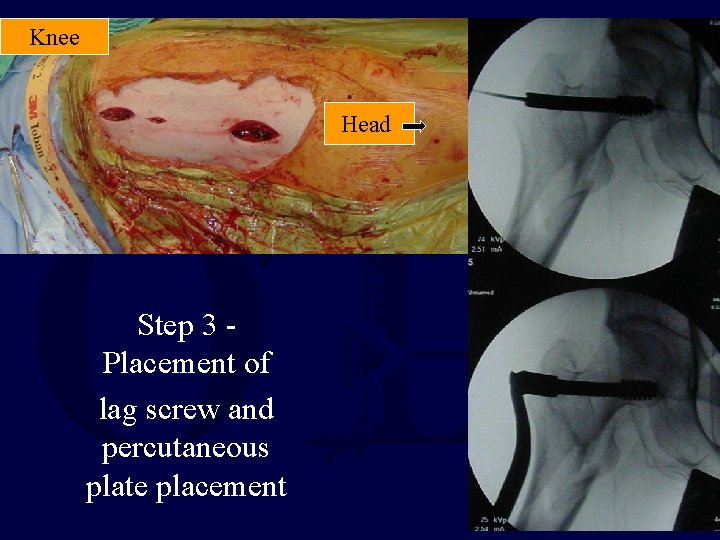

Knee Head Step 3 Placement of lag screw and percutaneous plate placement